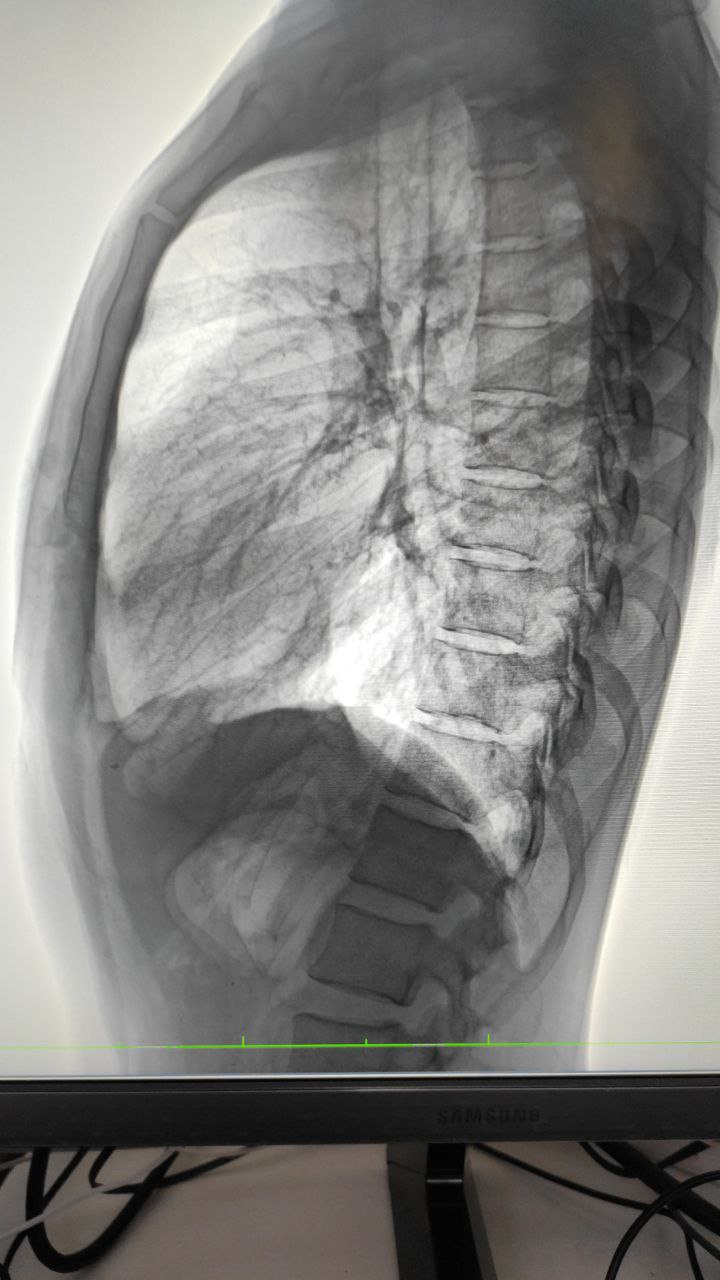

Доброй ночи. Анамнез неизвестен, жалоб нет

Какие мысли?